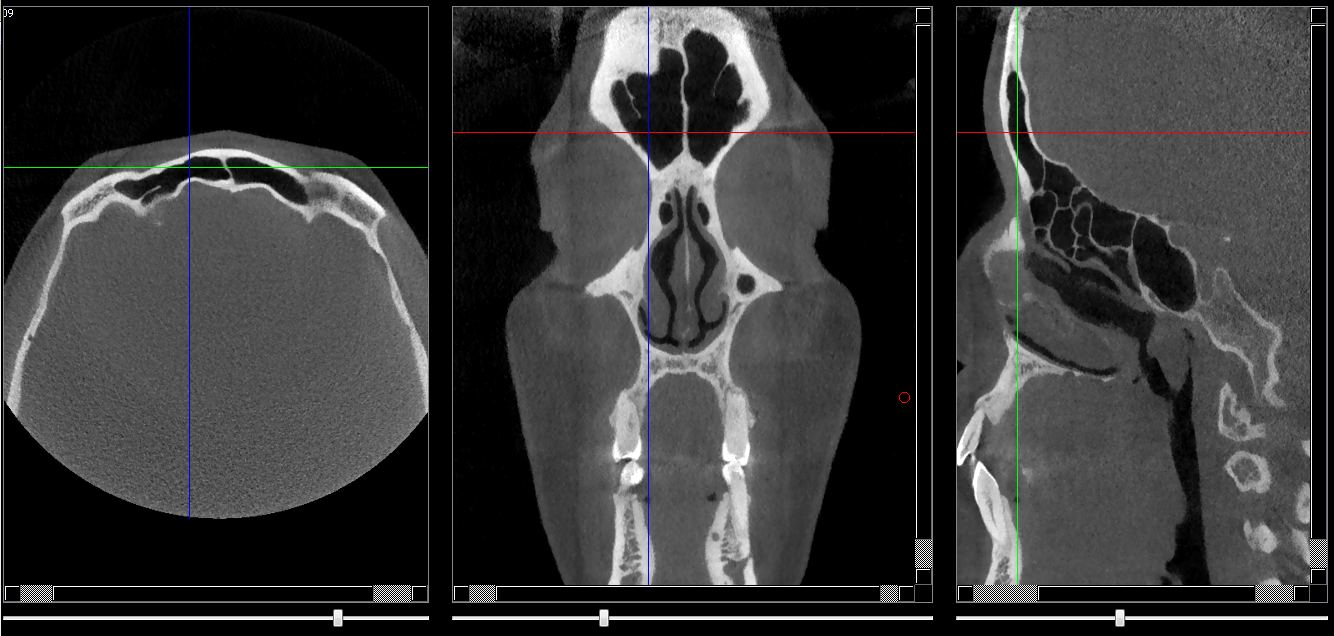

Structures osseuses

Sinus frontal

Repères anatomiques

- Coupe transversale

- Début : Fissure orbitaire sup

- Fin : Os frontal

- Coupe frontale

- Début : Corticale externe de l'os frontale

- Fin : Corticale interne de l'os frontale

- Coupe saggitale

- Début : Corticale externe droite de l'os frontal

- Fin : Corticale externe gauche de l'os frontal